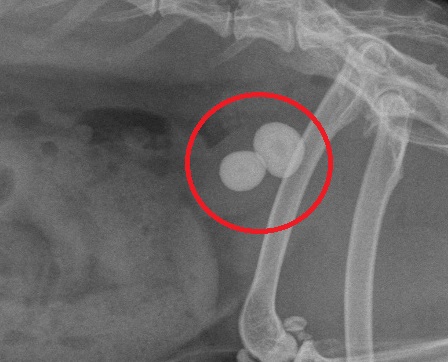

Röntgenfoto van Snuf met twee enorme blaasstenen duidelijk zichtbaar

Deze blaasstenen zorgen voor de steeds terugkerende blaasklachten

Omdat de stenen te groot zijn om uit te plassen moeten ze operatief worden verwijderd